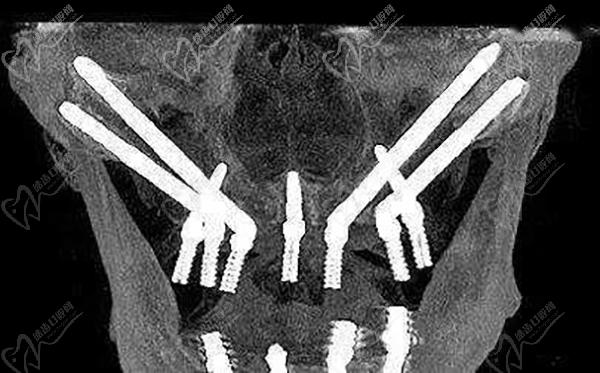

全口即拔即種即刻負(fù)重種植牙一般分為兩期,一期手術(shù)是在拔除牙齒后立即植入種植體,戴臨時(shí)牙冠,等待創(chuàng)口愈合;二期手術(shù)則是待創(chuàng)口愈合后,進(jìn)行固定牙冠佩戴。全口即拔即種即刻負(fù)重可以同時(shí)全口做,也可以先上頜后下頜。在每期手術(shù)之間,醫(yī)生會根據(jù)患者的具體情況進(jìn)行相應(yīng)的藥物治療和護(hù)理指導(dǎo)。

牙友1、前天結(jié)束的全口種植牙,拔牙加同期種12顆瑞士士卓曼,即刻負(fù)重!全口牙周炎伴隨多顆牙松動且骨量不足等問題,普通的種植手術(shù)無法滿足生活需求,想要做即拔即種即刻戴上臨時(shí)牙,因?yàn)槌R?guī)的植骨手術(shù)需要等待很長時(shí)間。經(jīng)過正規(guī)醫(yī)院骨質(zhì)評估分析,上頜AO4+兩邊穿翼手術(shù),患者手術(shù)結(jié)束當(dāng)天就可以正常用牙,本人表示非常高興和滿意!感謝醫(yī)院團(tuán)隊(duì)協(xié)作!